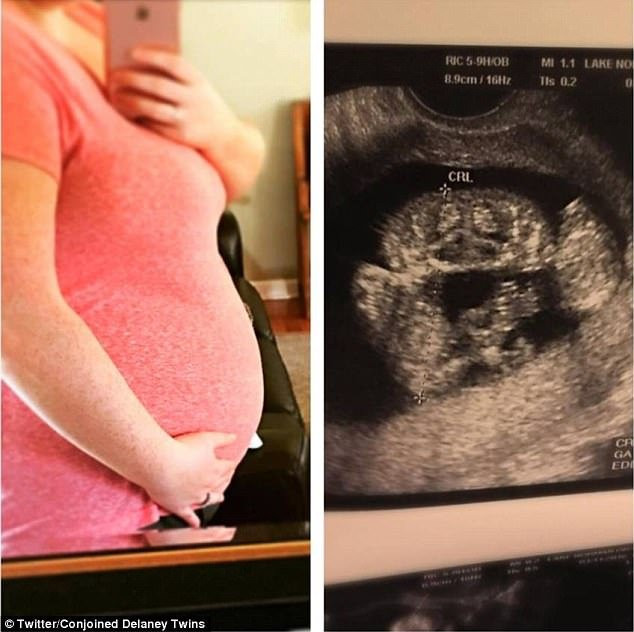

Hình chụp ảnh siêu âm khi mang thai của Heather.

Cha mẹ của 2 bé là Heather và Riley đã phát hiện ra 2 đứa con của mình bị dính liền từ khi thai mới được 11 tuần tuổi. Tuy nhiên, họ chưa bao giờ có ý định bỏ những đứa con gái của mình. Ngay sau đó, bệnh viện tuyên bố rằng họ bắt đầu phải thực hiện chế độ chăm sóc đặc biệt.